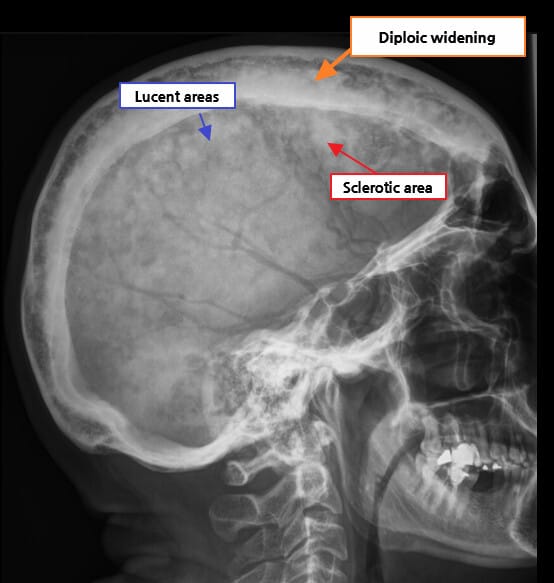

• Cotton wool: 중기 이후 혼합 및 경화 단계

🟦 Cotton wool appearance

두개골 등에서 관찰되며, 경화된 모호한 병변이 솜뭉치처럼 보이는 것이 특징입니다.